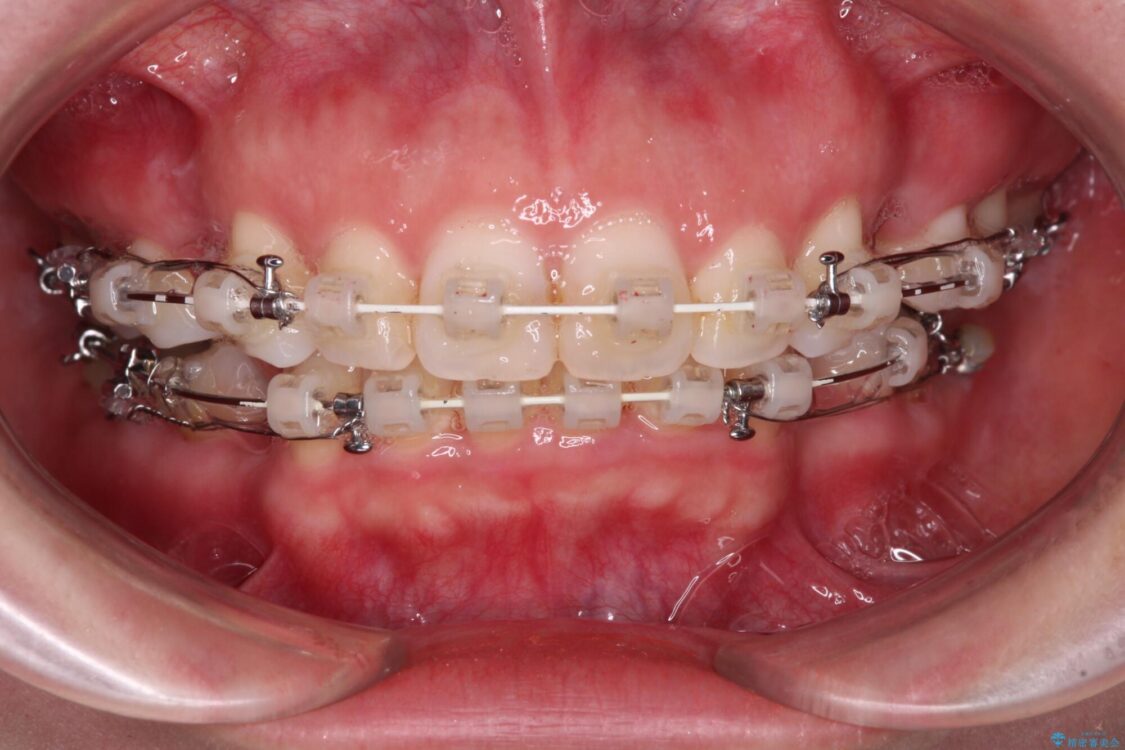

治療後について

奥歯の咬み合わせ改善には1年ほどの期間と処置中の噛みにくさを強いることとなりましたが、抜歯後はスムーズに治療を完了させることができました。

歯ぎしりの際に奥歯が干渉していた咬み合わせも理想的な状態に改善できました。

治療後

• 【モニター】出っ歯と咬み合わせを改善 ワイヤー装置の抜歯矯正 治療後画像